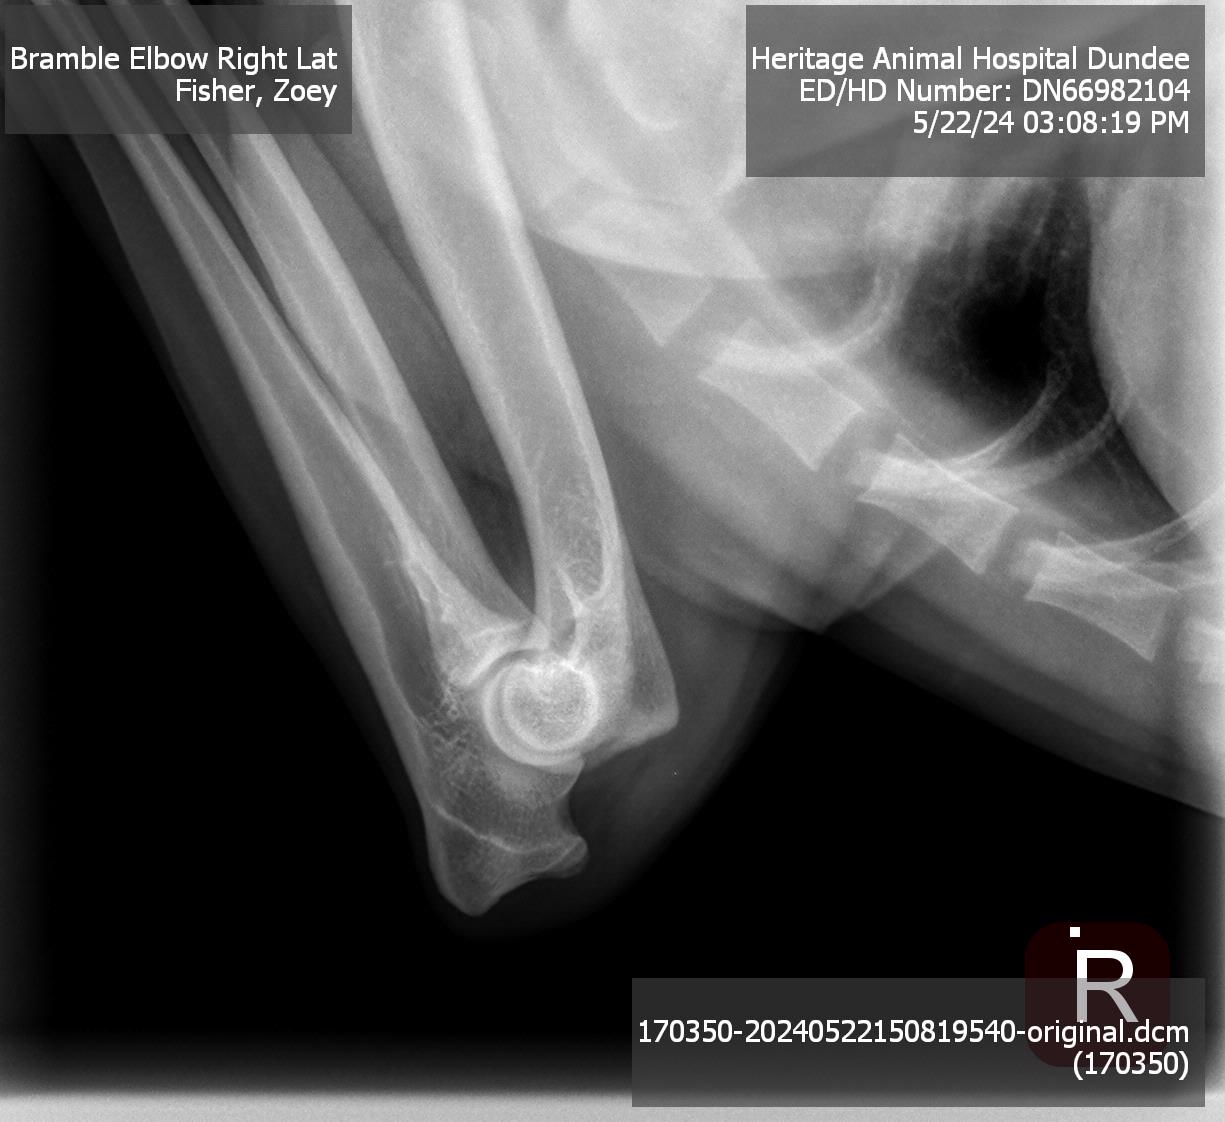

Elbows: |

Normal |

Pedigree | OFA Database Entry | Hips | Left Elbow | Right Elbow